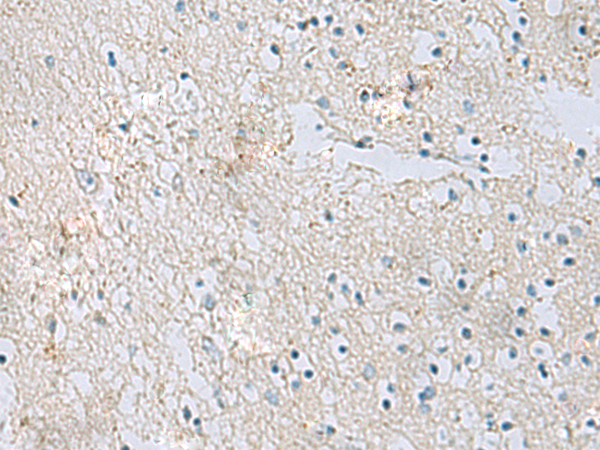

IHC positive control: |

Human brain |

IHC Recommend dilution: |

50-100 |